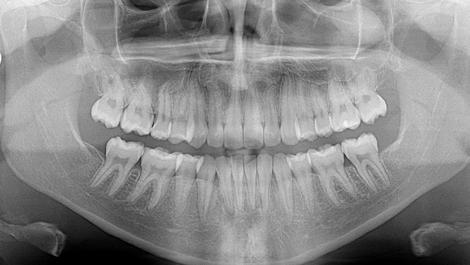

Cephalometric analysis confirmed a mild skeletal Class III relationship and normal vertical dimension. Both the maxillary and mandibular incisors were measurably mildly retroclined. The panoramic view was unremarkable. In fact, root length and bone level were excellent at the start of treatment.

The post-treatment panoramic radiograph (Figure 7) reveals little difference in size between the right and left maxillary second premolars, again suggesting that clinical crown length appears to be related to gingival coverage. The panorex also shows good root parallelism across the mandibular first premolar extraction sites. Root length and morphology suggest no obvious root resorption with time efficient treatment.